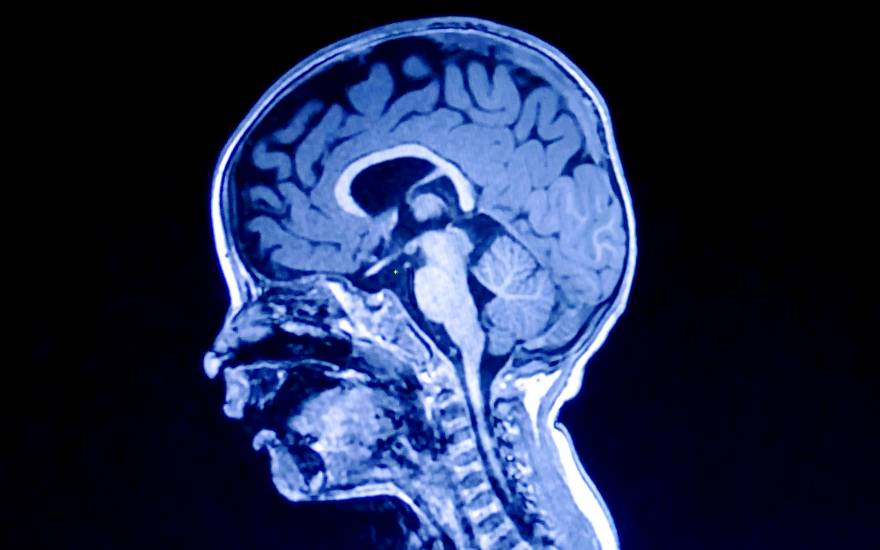

Los nuevos equipos de resonancia mejoran la capacidad diagnóstica en el cerebro pediátrico

La resonancia magnética es la prueba de elección cuando se quiere analizar el cerebro de los niños. Tiene alta resolución, no emite radiación ionizante y ha mejorado su capacidad diagnóstica debido a que los nuevos equipos han reducido el tiempo necesario para realizar las pruebas, lo que permite un menor tiempo de sedación en caso de bebés y niños de corta edad. Así lo demuestran las pruebas que viene realizando el Hospital Universitario Quirónsalud Madrid a partir de la incorporación de nuevos equipos con tecnología de GE Healthcare que, además permiten corregir pequeños movimientos del niño durante la prueba y ofrecen a los radiólogos la posibilidad de acceder a modos de visualización de las imágenes diagnósticas que se apoyan en la inteligencia artificial para ayudar al diagnóstico. Un ejemplo de este uso es la recolocación automática, con la que se estudia el cerebro de los niños siempre en la misma posición independientemente de cómo se coloquen al realizar la prueba.

"Los nuevos equipos permiten obtener imágenes en las que se aprecia el cerebro del menor en los tres planos del espacio sin perder calidad con grosores de corte mínimos. Esta mayor resolución temporal y espacial tiene gran repercusión en el mundo pediátrico donde los volúmenes que estudiamos son muy pequeños y es muy útil no sólo en patología vascular y oncológica, sino también en el estudio de los trastornos del neurodesarrollo, como el trastorno por déficit de atención por hiperactividad y los trastornos del espectro autista", explica la Dra. Mar Jiménez

, jefa asociada del Servicio de Diagnóstico por la Imagen del Hospital Universitario Quirónsalud Madrid y especialista en el estudio del cerebro infantil. "Por otro lado, la mayor resolución nos ofrece la posibilidad de realizar estudios de la vascularización cerebral sin necesidad de contraste intravenoso", sostiene Jiménez.

Las resonancias magnéticas requieren de antenas que se colocan en la zona que se quiere estudiar y que recogen la información de la prueba. En este aspecto también se ha producido una mejora considerable con respecto a tecnologías anteriores: "Las nuevas antenas flexibles y con más número de canales ofrecen una imagen más homogénea del cerebro infantil, incrementando la señal significativamente y mejorando la capacidad diagnóstica. Además, permiten cubrir amplios espacios corporales, especialmente importantes en los estudios de cuello, plexo o médula espinal, con muy buena supresión de la grasa".

Como destaca la Dra. Jiménez, "la imagen diagnóstica ha sido siempre cualitativa, morfológica, pero cada vez se requiere más información cualitativa, cuantificable y numérica del estado del paciente que se pueda seguir en el tiempo. Se están desarrollando modos de visualización que permiten obtener información numérica de, por ejemplo, volumen de sustancia gris o sustancia blanca, grosor cortical o valores de flujo sanguíneo cortical que se pueden aplicar en la práctica clínica diaria".

Quirónsalud Madrid posee 4 resonancias magnéticas, 2 de 1,5 Tesla y 2 de 3 Tesla, una de ellas es una Sigma Premiere de GE Healthcare que posee un imán y unos gradientes más potentes lo que permiten imágenes con mayor resolución; además, destaca por la velocidad de adquisición de imagen (8 veces más rápida que los equipos convencionales), lo que incrementa las aplicaciones diagnósticas de este equipo, como la medición de perfusión cerebral sin contraste o el detalle los picos de metabolitos en técnicas espectroscópicas. La nueva resonancia también posee un túnel más ancho que las resonancias convencionales lo que redunda en la comodidad del los pacientes.